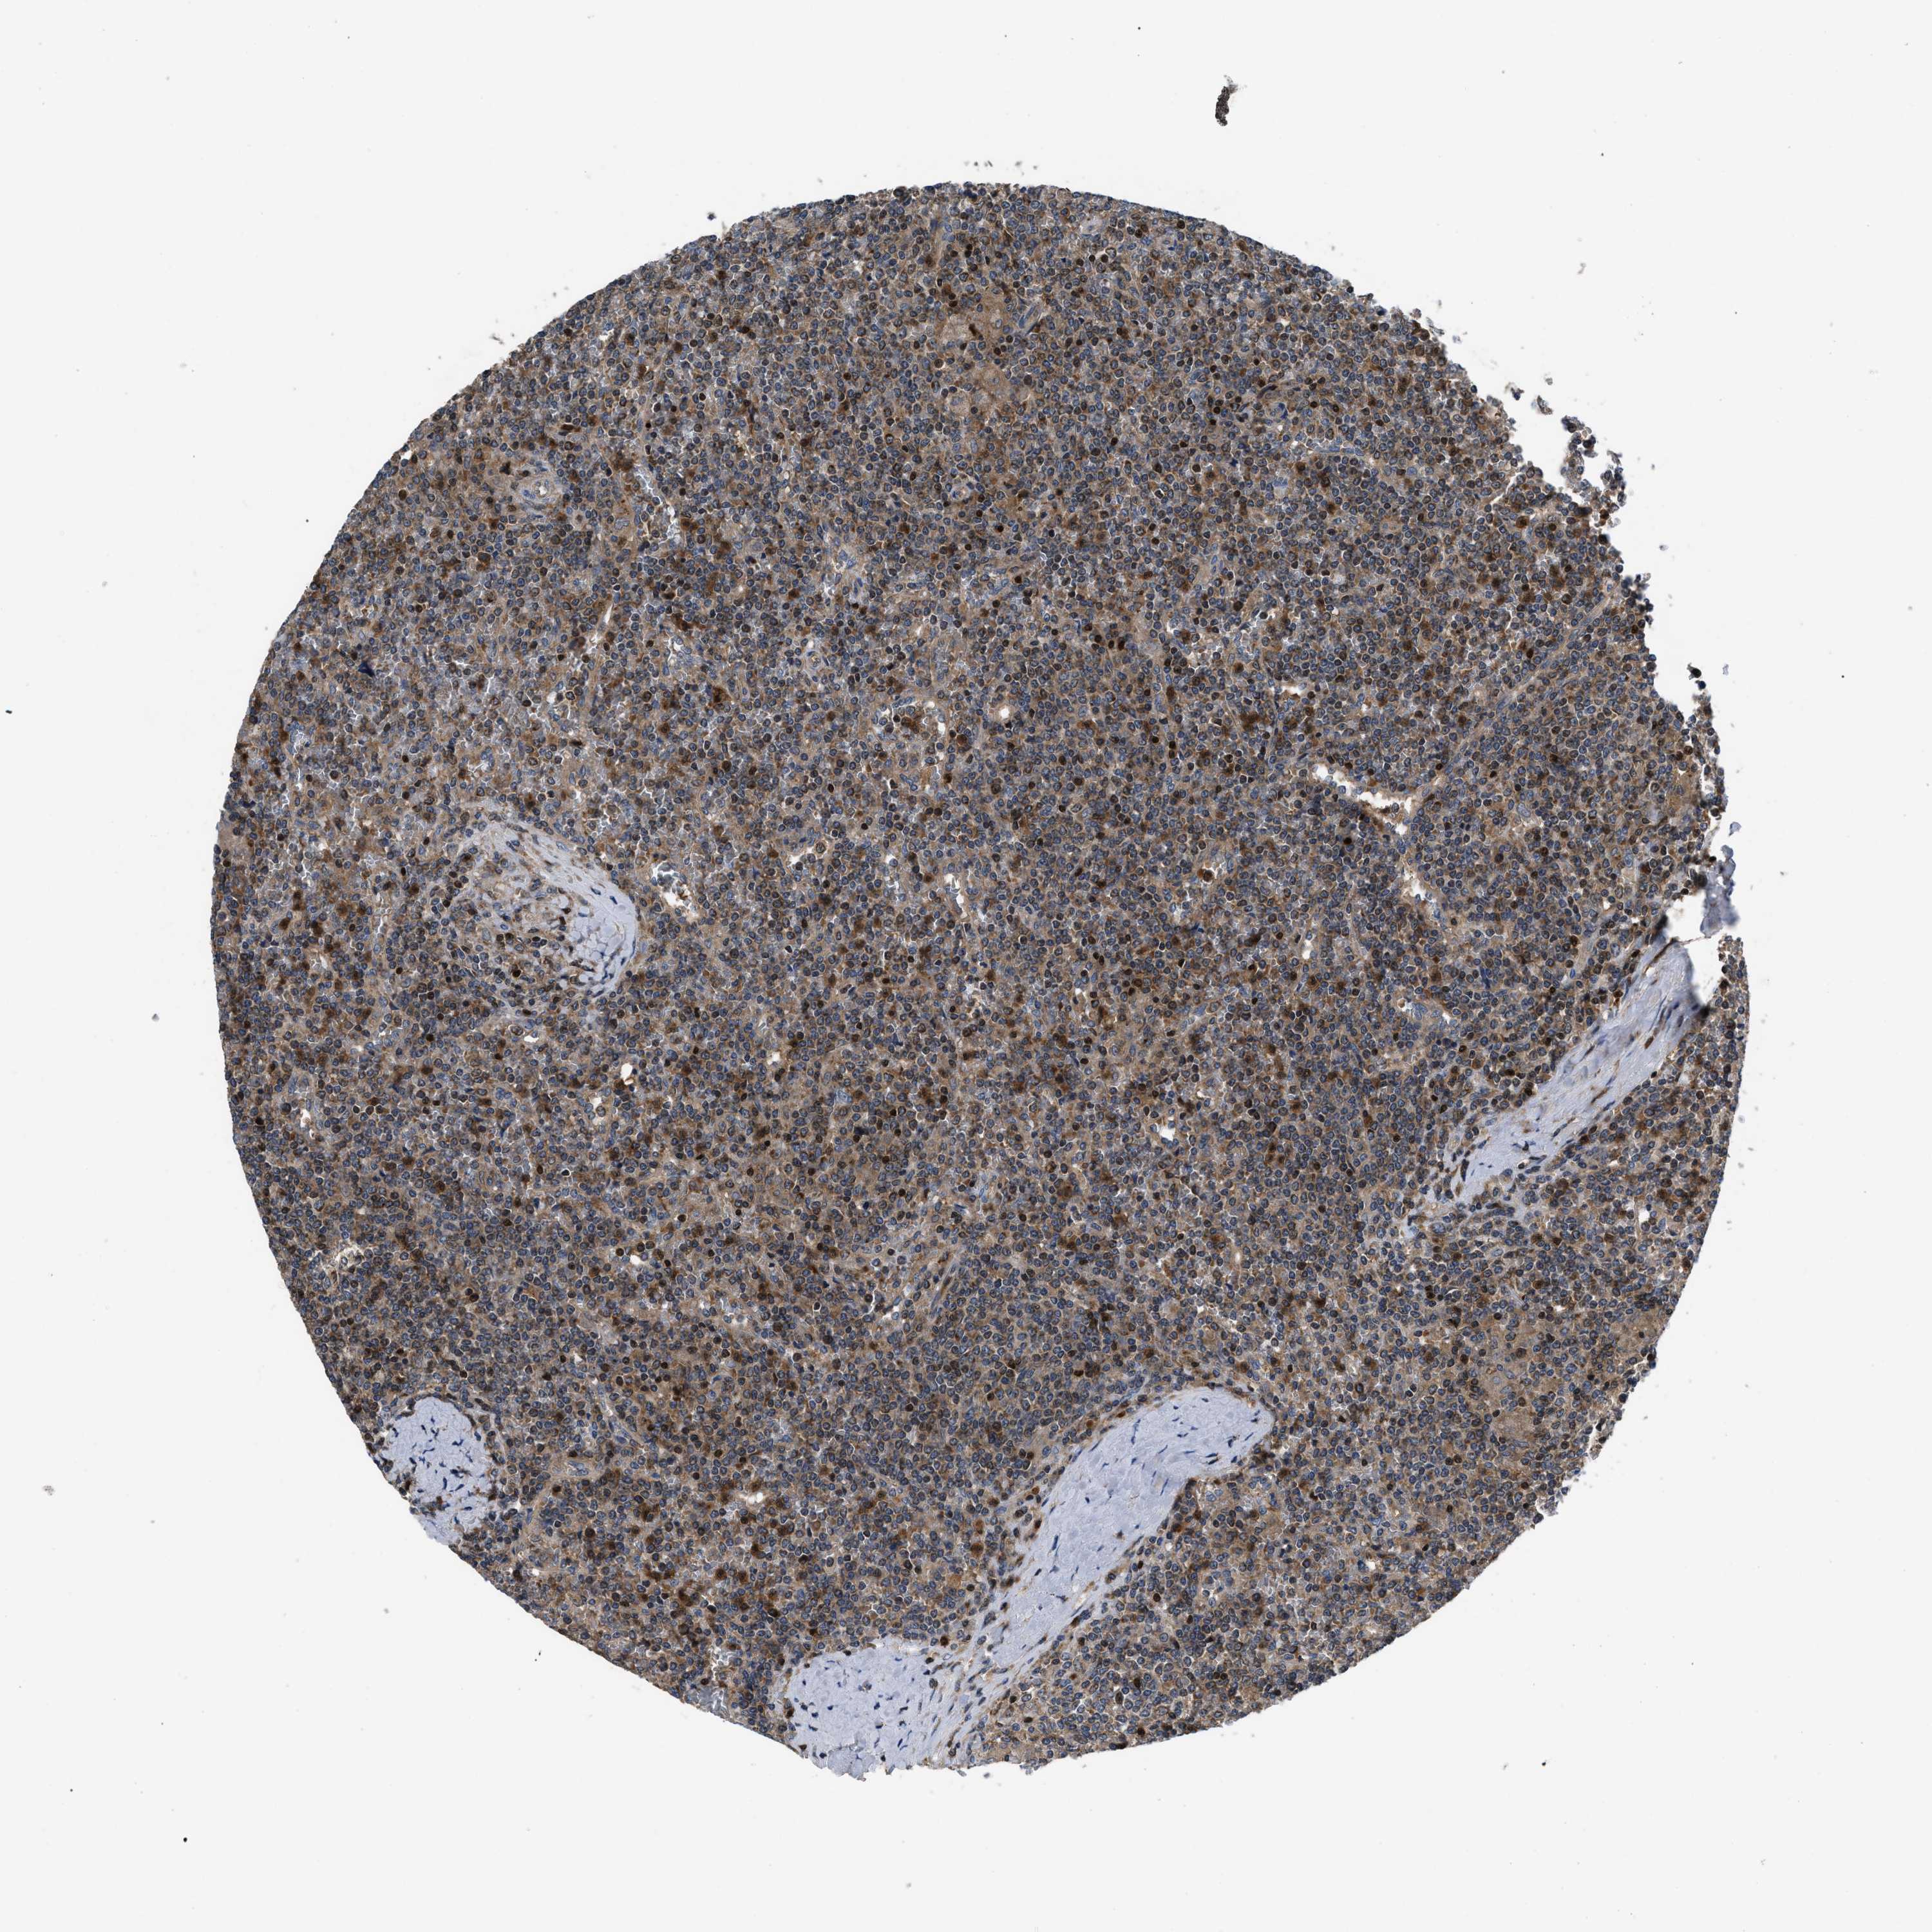

LYMPHOMA - Protein expressioni

A mouse-over function shows sample information and annotation data. Click on an image to view it in a full screen mode. Samples can be filtered based on level of antibody staining by selecting one or several of the following categories: high, medium, low and not detected. The assay and annotation is described here.

Antibody stainingi

Antibody staining in the annotated cell types in the current human tissue is reported as not detected, low, medium, or high, based on conventional immunohistochemistry profiling in selected tissues. This score is based on the combination of the staining intensity and fraction of stained cells.

Each image is clickable and will lead to virtual microscopy that enables deeper exploration of all samples and also displays staining intensity scores, fraction scores and subcellular localization as well as patient and tissue information for each sample.

Antibody HPA018162

Staining

High

Intensity

Strong

Quantity

>75%

Location

Nuclear

Hodgkin's disease, NOS

Malignant lymphoma, non-Hodgkin's type, High grade

Malignant lymphoma, non-Hodgkin's type, Low grade